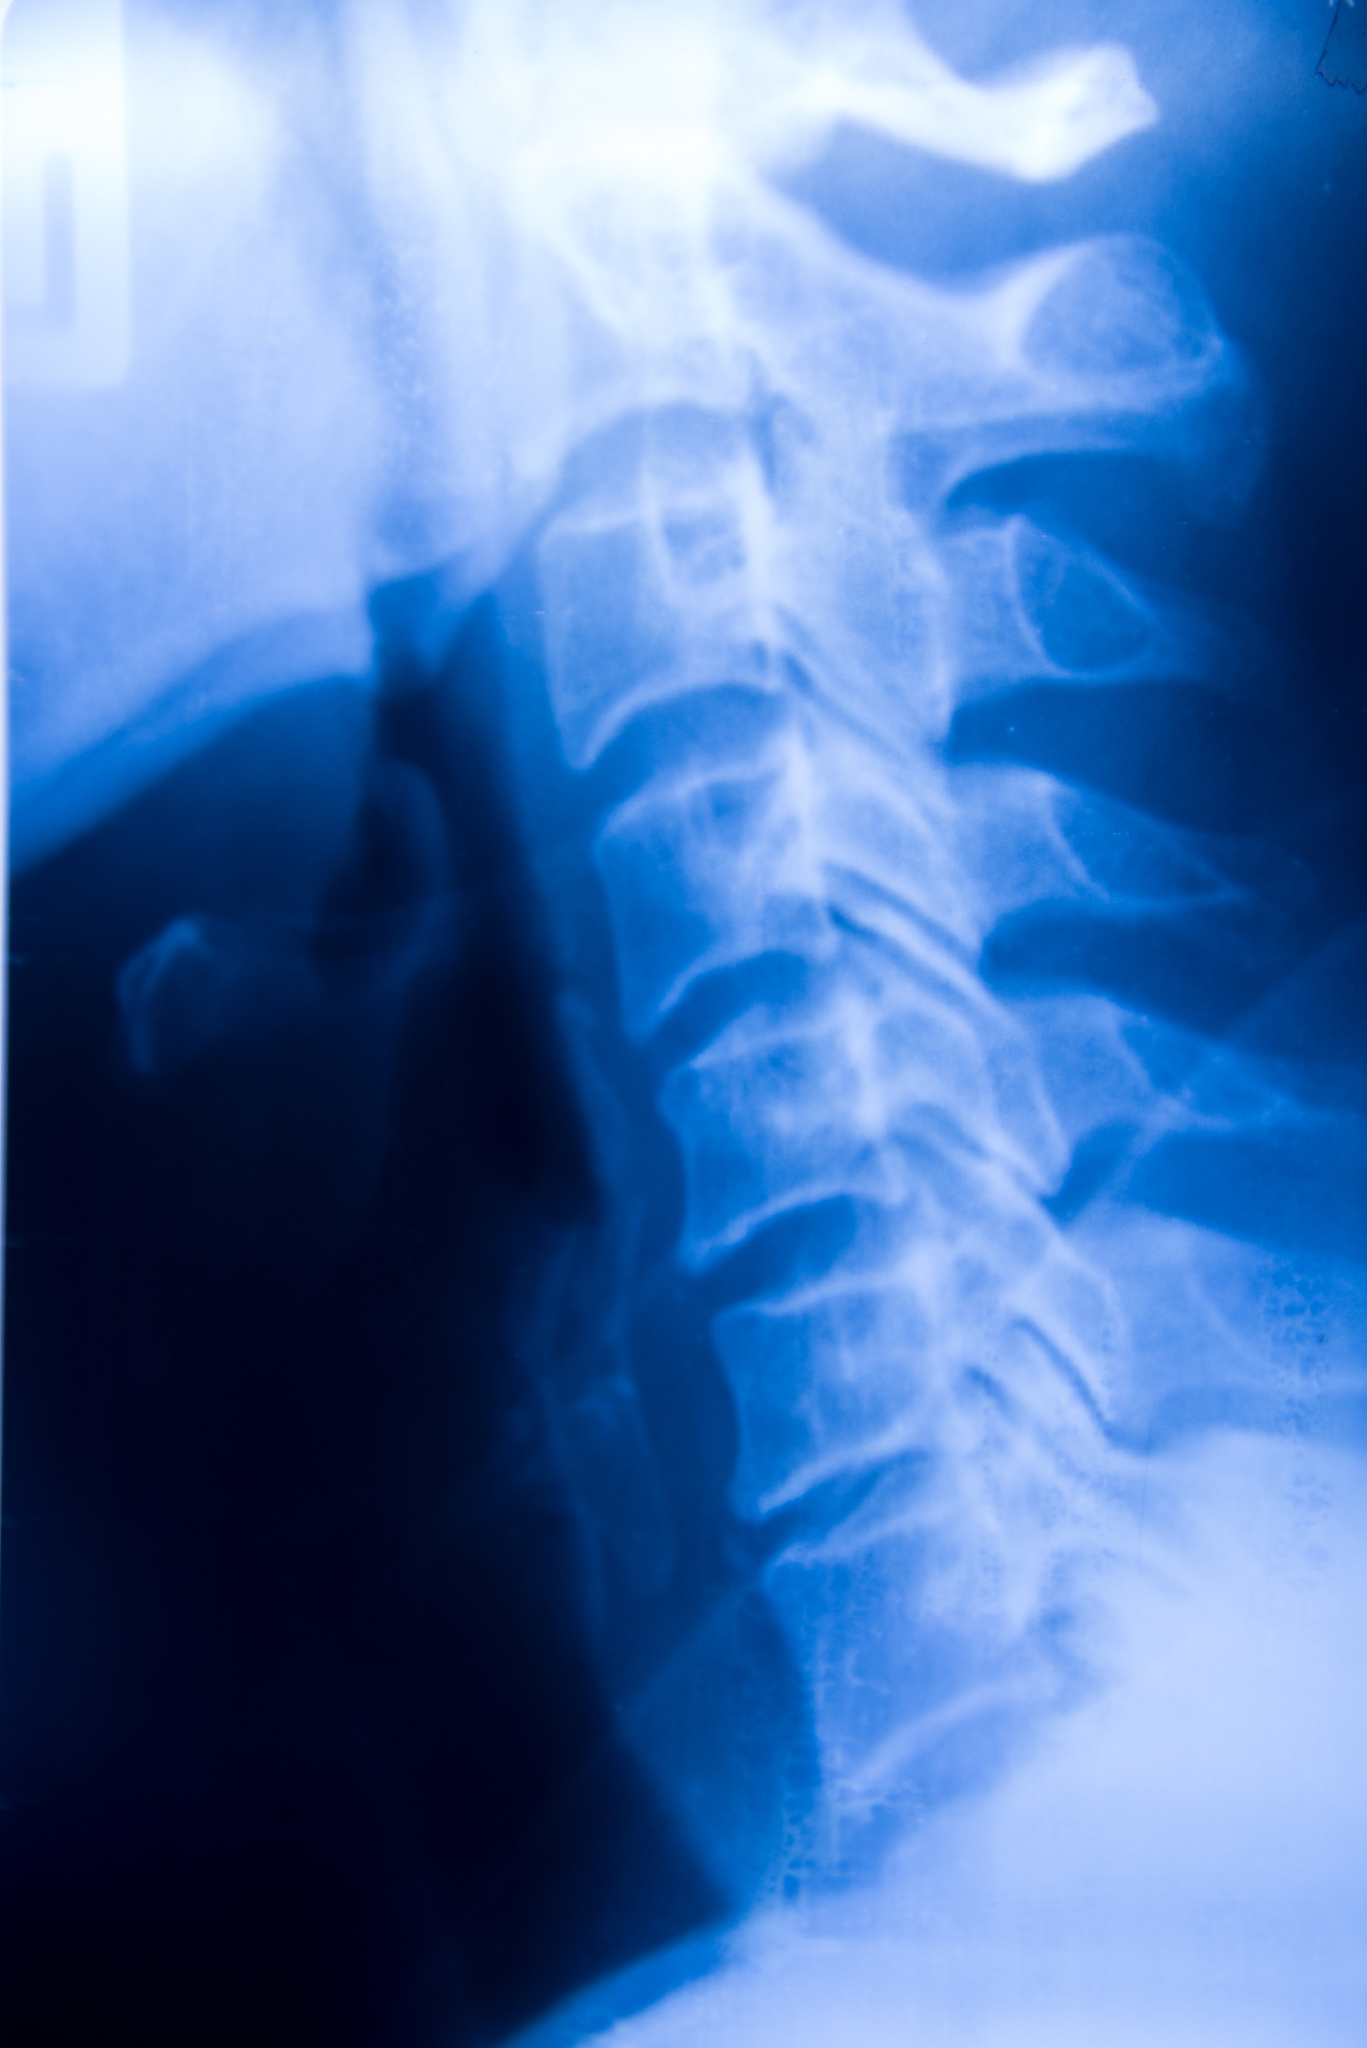

椎体成形术是一种采用特殊设备将骨水泥注入椎体内部的手术,适用于胸腰椎压缩骨折的治疗。其操作步骤如下:

2. 通过X线引导下,将特殊设备引入到椎体内。